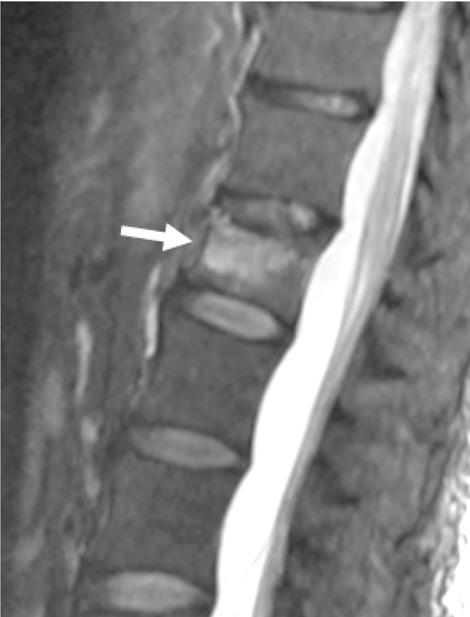

This study includes 22 vertebroplasty procedures performed from October 2018 to July 2020 in 21 patients with traumatic or osteoporotic vertebral fractures (19 female, two men; age between 53 and 89 years). All treatments were executed under fluoroscopic guidance using 11 or 13 G needle through transpedicular or costovertebral unilateral approach. Each patient underwent conscious sedation, continuously monitored by an anesthesiologist. Preoperative MRI images, obtained by 3T or 1.5T MRI scanner, always showed bone marrow edema. The VAS scale and Roland Morris disability questionnaire (RMdq) were administered to patients before and after the treatment to evaluate pain and life quality.

本研究纳入了 2018 年 10 月至 2020 年 7 月期间 21 例创伤性或骨质疏松性椎体骨折患者(19 名女性,2 名男性;年龄 53-89 岁)的 22 例椎体成形术。所有治疗均在透视引导下通过经皮或肋椎关节单侧入路,使用 11 或 13G 针进行。每位患者均在麻醉师的连续监测下接受清醒镇静。术前 MRI 图像由 3T 或 1.5T MRI 扫描仪获得,均显示骨髓水肿。在治疗前后,使用视觉模拟评分(VAS)量表和 Roland Morris 残疾问卷(RMdq)对患者进行疼痛和生活质量评估。